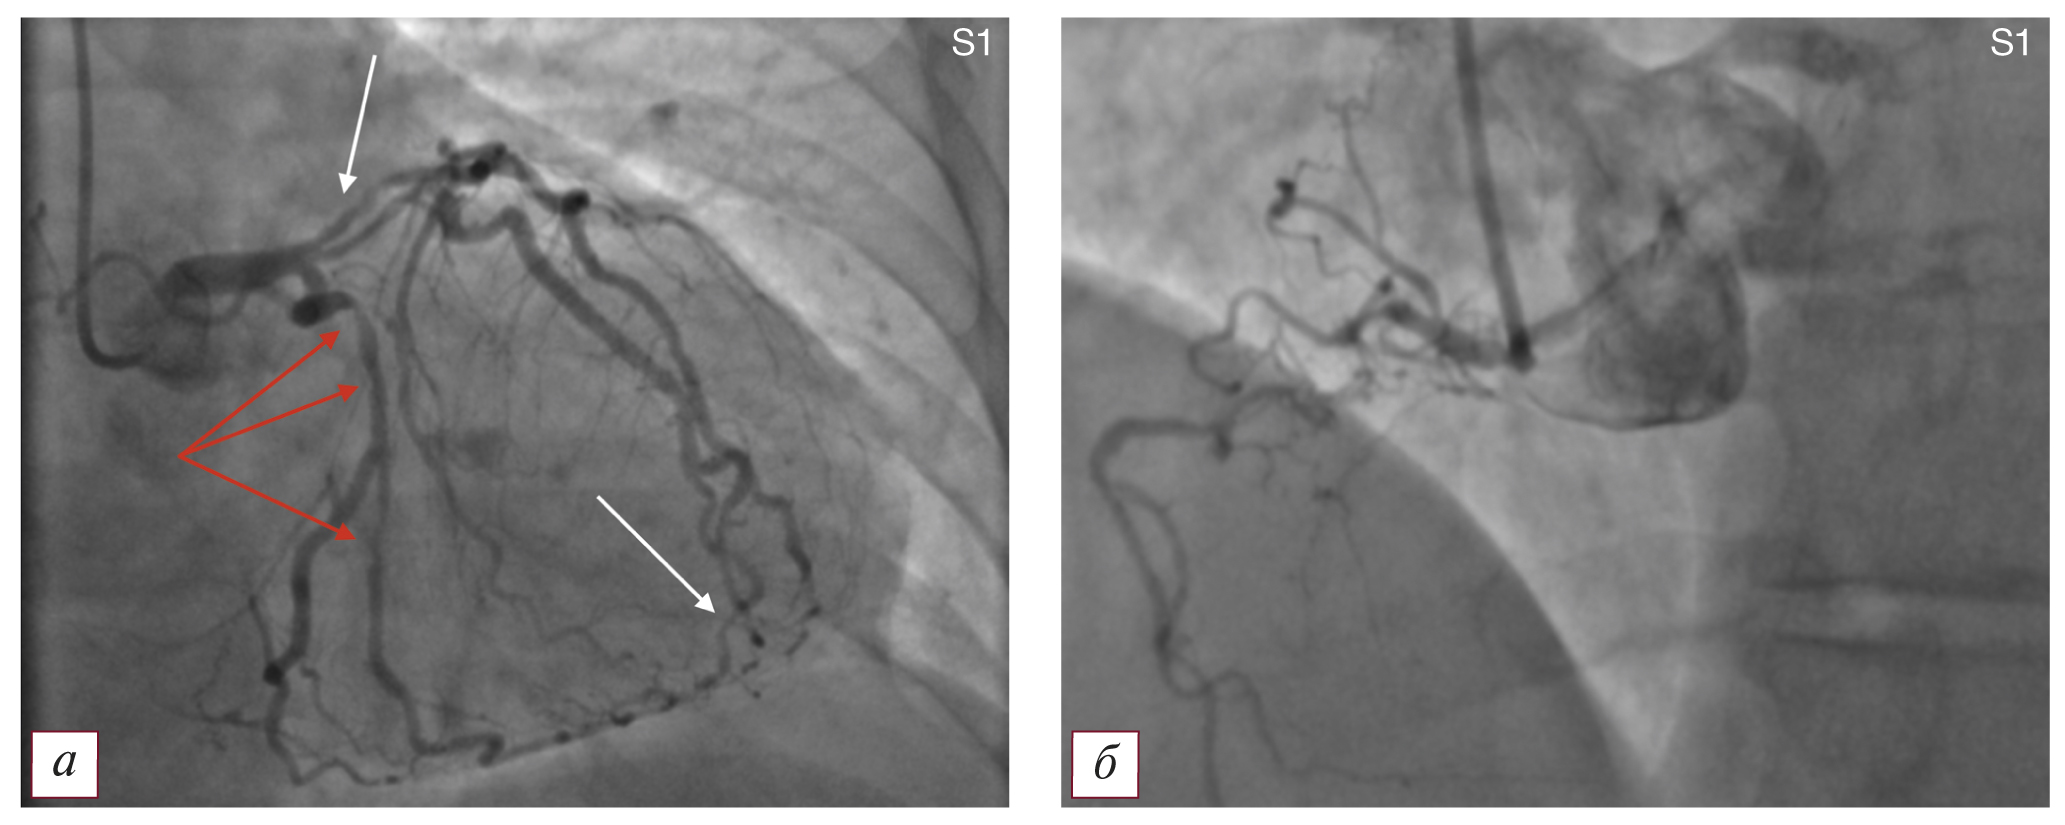

Тип S1 — ПАЛЖ и множественное гемодинамически значимое поражение крупных коронарных артерий и их ветвей без нарушения функции синусового узла или атриовентрикулярного узла при левом типе кровоснабжения миокарда (рис. 3).

Рис. 3. Коронароангиографическая картина поражения коронарного русла и постинфарктной аневризмы левого желудочка по типу S1: а — гемодинамически значимые стенозы проксимального и дистального отделов передней нисходящей артерии, проксимальной части 1-й диагональной артерии (указаны белыми стрелками), проксимальной половины огибающей артерии и ее ветвей (указаны красными стрелками); б — правая коронарная артерия. / Fig. 3. Coronary angiographic picture of the lesion of the coronary bed and postinfarction aneurysm of the left ventricle type S1: а — hemodynamically significant stenoses of the proximal and distal parts of the anterior descending artery, the proximal part of the 1st diagonal artery (indicated by white arrows), the proximal half of the envelope artery and its branches (indicated by red arrows); б — the right coronary artery.